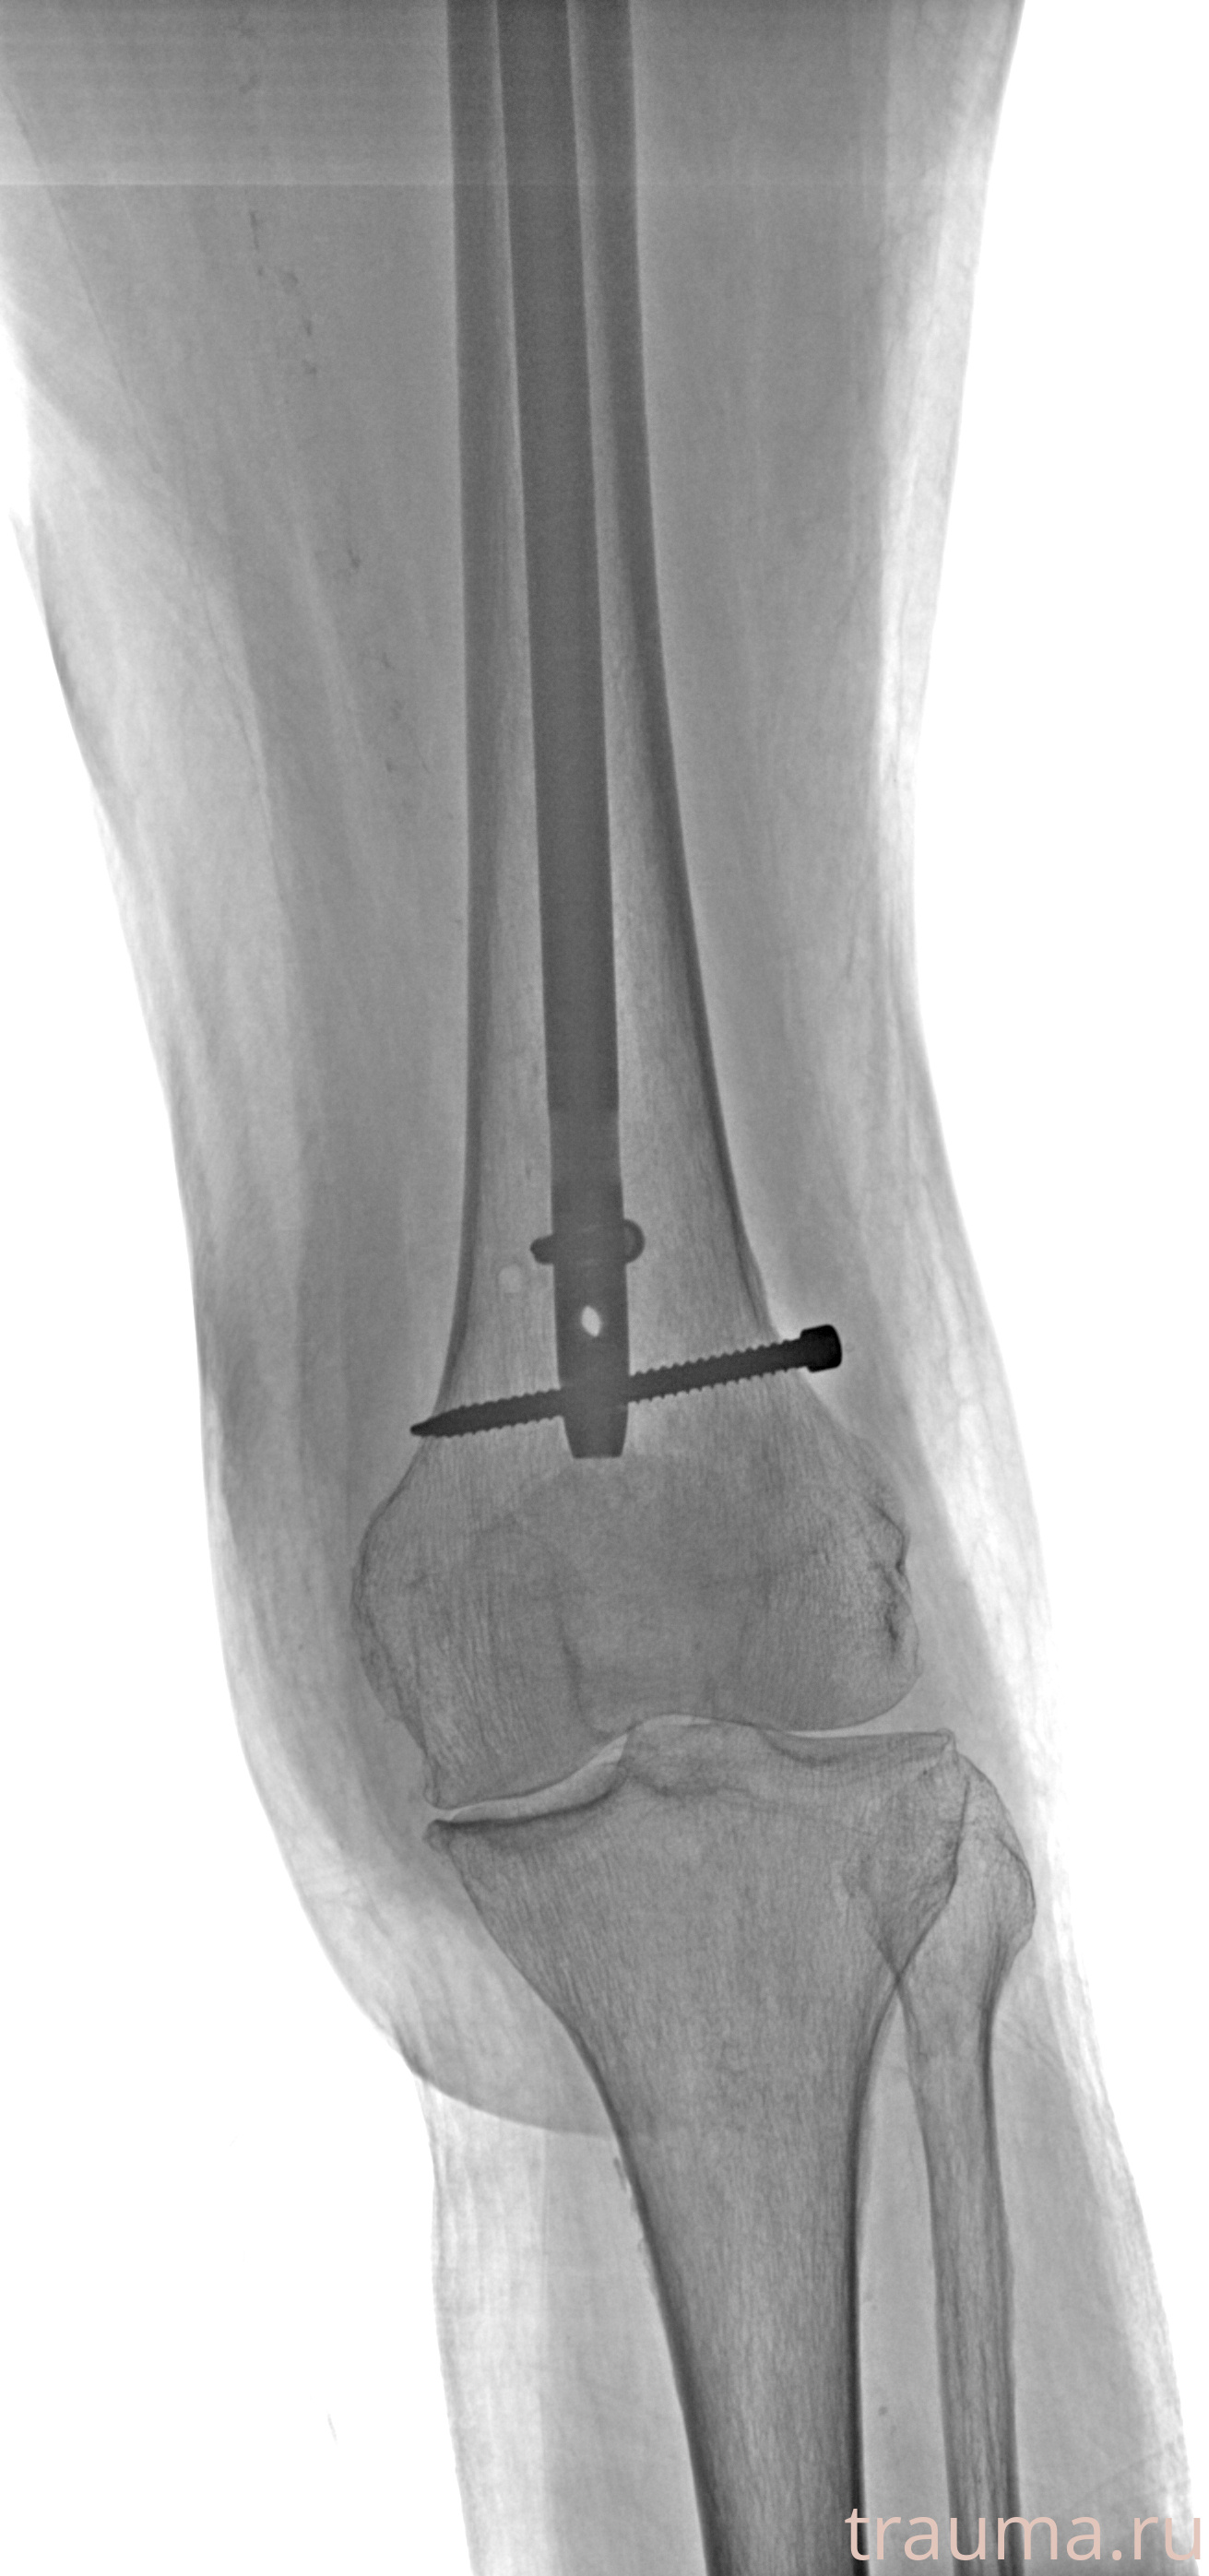

Рентгенограммы

Рентген на дому: по вашему адресу приезжает врач-рентгенолог, травматолог-ортопед с мобильным рентгеновским аппаратом, проводит диагностику травмы или заболевания, делает необходимые рентгенограммы, дает рекомендации по дальнейшему лечению. Получить качественные снимки в домашних условиях возможно благодаря уникальной методике, разработанной МосРентген Центром для института  Склифосовского